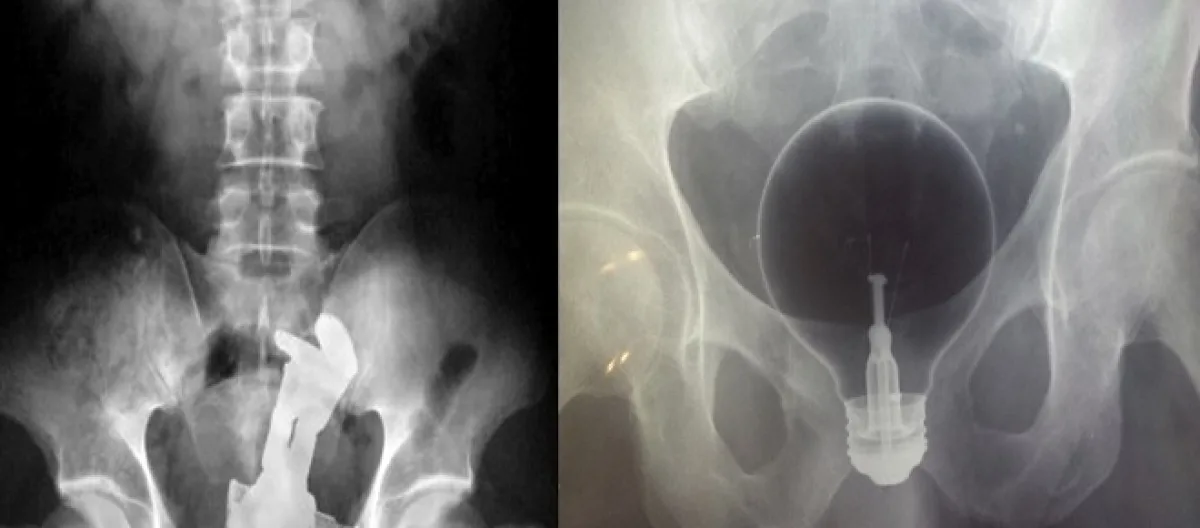

10- Uma lâmpada muito resistente.

Seja qual for, algumas pessoas acabam colocando em risco sua vida. Introduzir ou engolir uma faca, ou uma lâmpada, ou um copo pode trazer perigo real à vida. A faca pode cortar a pessoa por dentro, já a lâmpada e o copo podem quebrar e causar sérios ferimentos e até hemorragia, acabando por levar a pessoa a óbito.